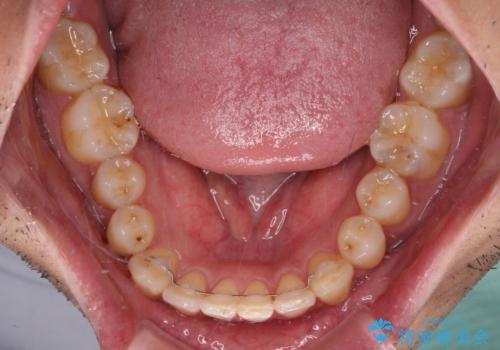

部分矯正は咬み合わせが不安定になったり、スペースができてしまったりと、適用となる患者様は極めて限られますが、こちらの方はスムーズに治療を終えることができました。